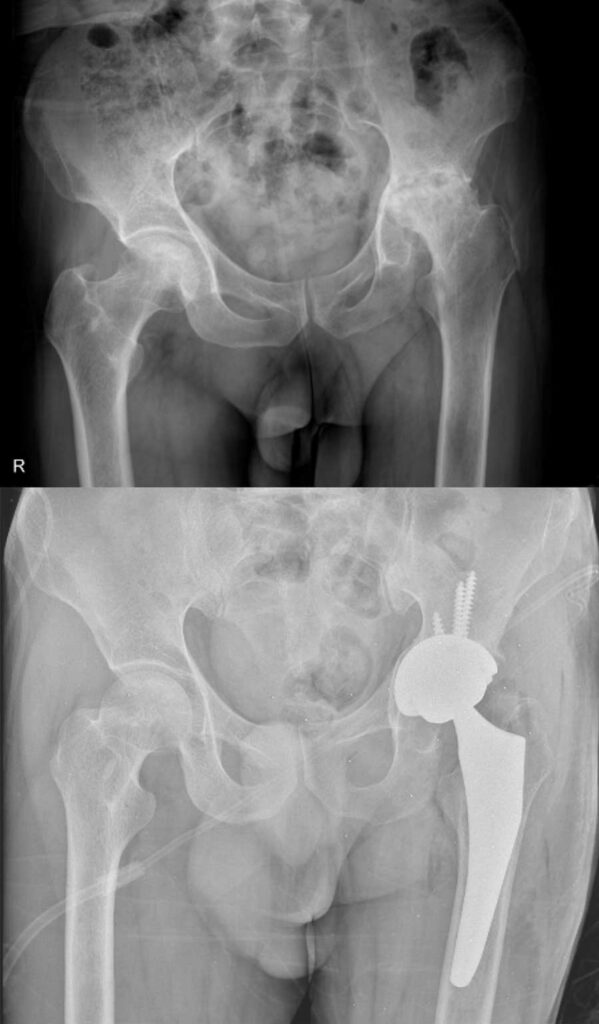

عکس تعویض مفصل لگن

برای آشنایی با تصاویر واقعی رادیوگرافی لگن قبل و بعد از جراحی، عکس تعویض مفصل لگن چند بیمار در زیر وجود دارد. با کلیک بر روی هر کدام از آنها تصویر بزرگتر و کامل را خواهید دید.